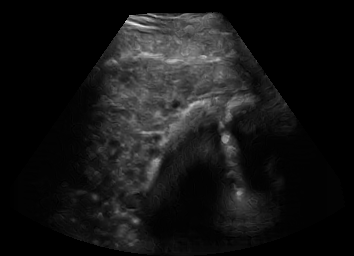

Real in-vivo images. 22 ultrasound sequences were collected using a GE Voluson E8 machine during standard fetal screening exams of 8 patients. Each sequence is several seconds long. We extracted all 4427 frames and resize them to , see Fig. 2 for some examples. The resulting image set was randomly split into training-validation-test sets by a 80-10-10% ratio.